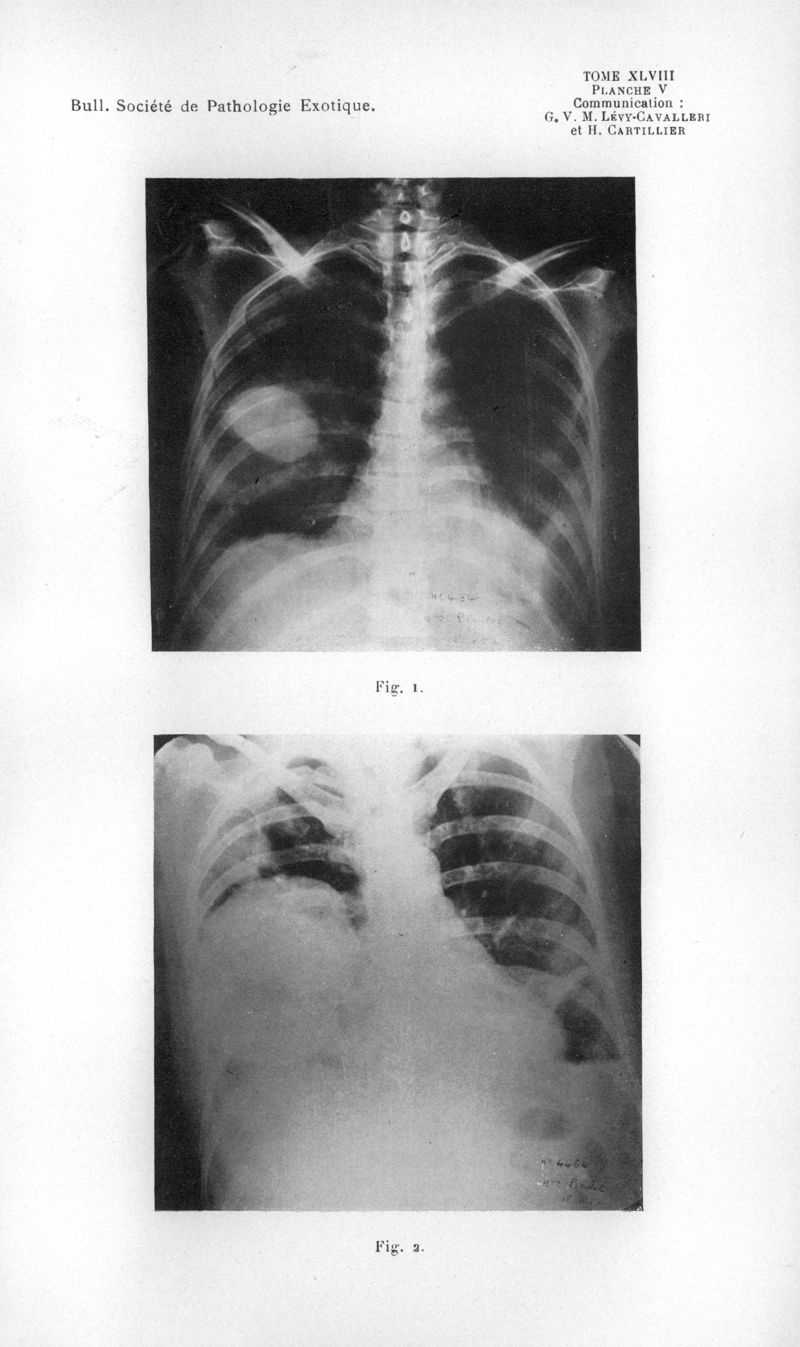

Bulletin de la Société de pathologie exotique et de ses filiales

1955, tome 48. - Paris : Masson, 1955.